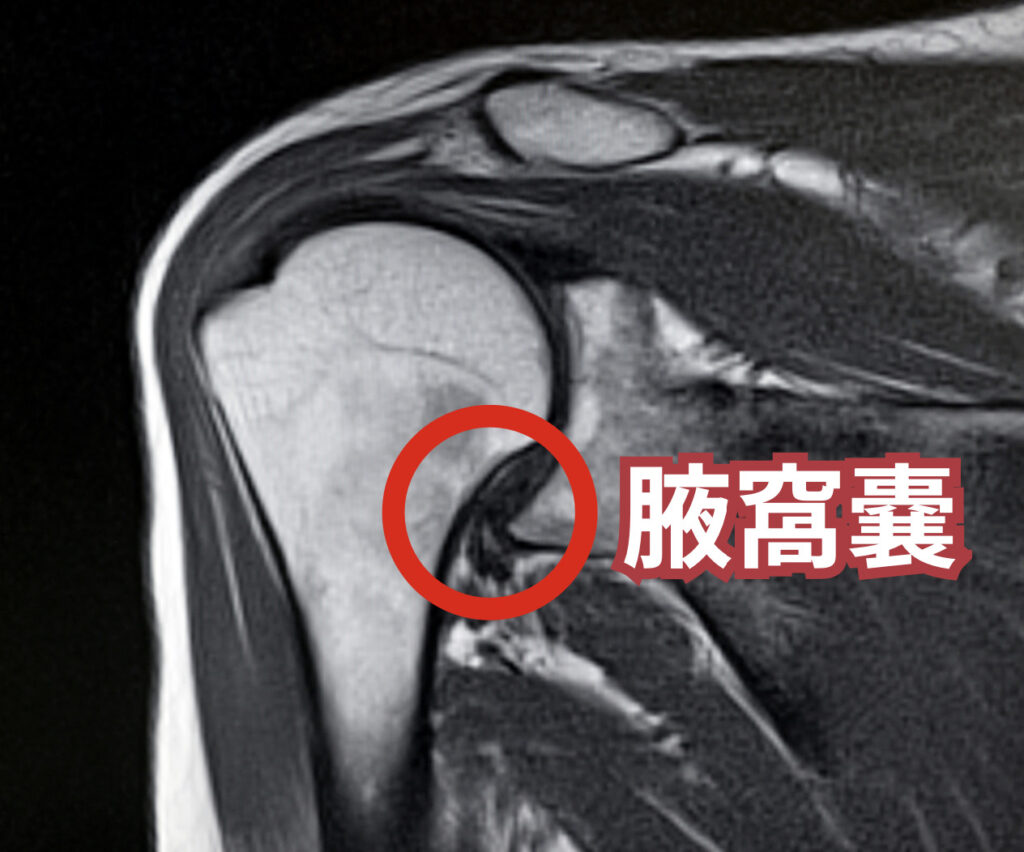

次に、石灰沈着性腱板炎のMRI検査です。レントゲンでは骨しか映りませんが、MRIは関節包、腱板(インナーマッスル)、筋肉、水(炎症)などを詳細に映し出すことができます。

五十肩(凍結肩)では「MRIでも異常なし」と言われることもありますが、専門家が見れば典型的な所見があります。

関節の下方にある「腋窩(えきか)」と呼ばれる部分の関節包が分厚くなっていたり、関節の前方にある「腱板疎部(けんばんそぶ)」という部分に炎症の所見が見られたりします。

所見としての「変化」とは、具体的には、関節包が分厚くなっていること(肥厚)、あるいは炎症によって白く光って見えること(高信号)です。

また、上腕二頭筋長頭腱の「周り」に水が溜まる(水腫)所見もよく見られますが、これは「安易な診断(上腕二頭筋長頭腱炎)への警鐘」で申し上げた通り、凍結肩によって関節液(お水)の行き場がなくなって、腱の通り道に押し出されているだけ、ということがよくあります。

石灰沈着性腱板炎のMRI画像での見え方

実際のMRI画像(フリー素材より引用)では、関節の下方(腋窩)の部分がやや分厚くなっている様子が伺えます。重症な場合は、もっと分厚く、そして白く光る炎症所見が強くなります。